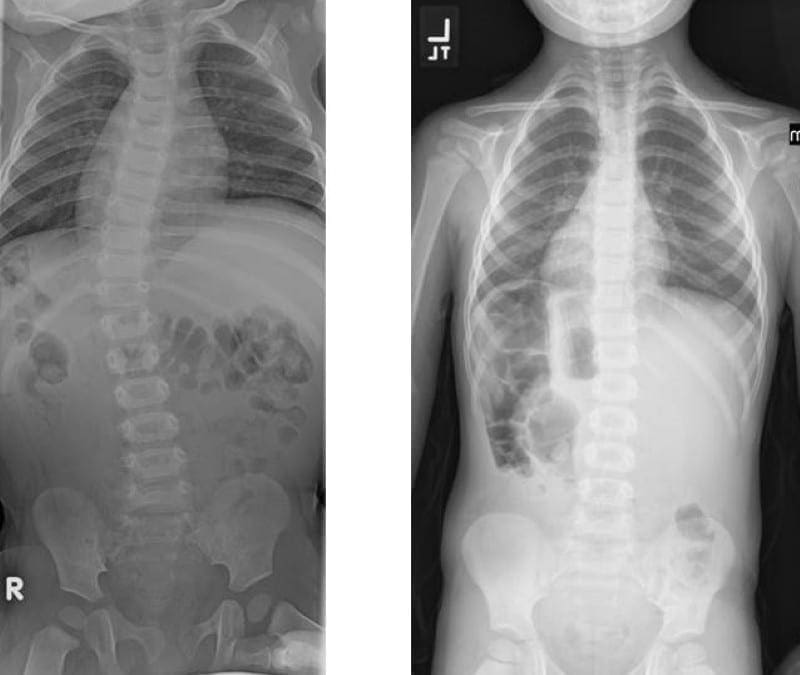

Studji dwar l-Immaġini

L-immaġini f'mard deġenerattiv tad-diska tintuża prinċipalment biex tiddeskrivi relazzjonijiet anatomiċi u karatteristiċi morfoloġiċi tad-diski affettwati, li għandha valur terapewtiku kbir fit-teħid ta 'deċiżjonijiet futuri għal għażliet ta' trattament. Kwalunkwe metodu ta 'immaġini, bħal radjografija sempliċi, CT, jew MRI, jista' jipprovdi informazzjoni utli. Madankollu, kawża sottostanti tista 'tinstab biss fi 15% tal-pazjenti billi l-ebda bidliet radjoloġiċi ċari ma huma viżibbli f'mard deġenerattiv tad-diska fin-nuqqas ta' ħernja tad-diska u defiċit newroloġiku. Barra minn hekk, m'hemm l-ebda korrelazzjoni bejn il-bidliet anatomiċi li dehru fuq l-immaġini u s-severità tas-sintomi, għalkemm hemm korrelazzjonijiet bejn in-numru ta 'osteofiti u s-severità ta' uġigħ fid-dahar. Bidliet deġenerattivi fir-radjografija jistgħu jidhru wkoll f'nies bla sintomi li jwasslu għal diffikultà biex jikkonformaw ir-rilevanza klinika u meta tibda l-kura. ("Marda tad-Diska Deġenerattiva" Fiżjopedja)

Ir-Radjografija

Din ir-radjografija ċervikali sempliċi rħisa u disponibbli b'mod wiesa 'tista' tagħti informazzjoni importanti dwar id-deformitajiet, l-allinjament, u bidliet deġenerattivi taż-żaqq. Sabiex tiġi ddeterminata l-preżenza ta 'instabilità ta' l-ispina u bilanċ sagittali, għandhom isiru studji ta 'flessjoni dinamika jew estensjoni.

Immaġini b'Reżonanza Manjetika (MRI)

L-MRI huwa l-iktar metodu użat komunement għad-dijanjosi ta 'bidliet deġenerattivi fid-diska intervertebrali b'mod preċiż, affidabbli, u l-iktar komprensiv. Jintuża fl-evalwazzjoni inizjali ta 'pazjenti b'uġigħ fl-għonq wara radjografija sempliċi. Jista 'jipprovdi immaġini mhux invażivi f'diversi pjanuri u jagħti immaġini ta' kwalità eċċellenti tad-diska. L-MRI tista 'turi l-idratazzjoni tad-diska u l-morfoloġija bbażata fuq id-densità tal-proton, l-ambjent kimiku, u l-kontenut ta' ilma. L-istampa klinika u l-istorja tal-pazjent għandhom jiġu kkunsidrati meta jiġu interpretati r-rapporti tal-MRI peress li ntwera li sa 25% tar-radjoloġisti jibdlu r-rapport tagħhom meta d-dejta klinika tkun disponibbli. Fonar ipproduċa l-ewwel skaner MRI miftuħ bil-kapaċità tal-pazjent li jiġi skannjat f'pożizzjonijiet differenti bħal wieqaf, bilqiegħda u liwi. Minħabba dawn il-karatteristiċi uniċi, dan l-iskaner MRI miftuħ jista 'jintuża għall-iskannjar ta' pazjenti f'qagħdiet li jġorru l-piż u qagħdiet bil-wieqfa biex jindividwaw bidliet patoloġiċi sottostanti li ġeneralment jiġu injorati fl-iskan MRI konvenzjonali bħal mard deġenerattiv tal-ġenbejn bil-ħernja. Din il-magna hija tajba wkoll għal pazjenti klawstrofobiċi, peress li huma jaraw skrin kbir tat-televiżjoni waqt il-proċess tal-iskannjar. ("Marda tad-Diska Deġenerattiva: Sfond, Anatomija, Patofiżjoloġija.")

Nucleus pulposus u annulus fibrosus tad-diska jistgħu ġeneralment jiġu identifikati fuq l-MRI, u dan iwassal għall-iskoperta ta 'herniation tad-diska bħala kontenuta u mhux kontenuta. Peress li l-MRI tista 'turi wkoll tiċrit annulari u l-ligament lonġitudinali posterjuri, tista' tintuża biex tikklassifika l-herniation. Dan jista 'jkun minfuq annulari sempliċi biex tittrasferixxi l-hernjazzjonijiet tad-diska tal-frammenti. Din l-informazzjoni tista 'tiddeskrivi diski patoloġiċi bħal diski estrużi, diski maħruġa u diski migrati.

Hemm diversi sistemi ta 'klassifikazzjoni bbażati fuq l-intensità tas-sinjal MRI, l-għoli tad-diska, id-distinzjoni bejn in-nukleu u l-annulus, u l-istruttura tad-diska. Il-metodu, minn Pfirrmann et al, ġie applikat b'mod wiesa 'u aċċettat klinikament. Skont is-sistema modifikata, hemm 8 gradi għall-mard deġenerattiv tad-diska lumbari. Il-Grad 1 jirrappreżenta diska intervertebrali normali u l-grad 8 jikkorrispondi mal-istadju tat-tmiem tad-deġenerazzjoni, li juri l-progressjoni tal-marda tad-diska. Hemm immaġini korrispondenti biex jgħinu d-dijanjosi. Peress li jipprovdu differenzjazzjoni tajba tat-tessut u deskrizzjoni dettaljata ta 'l-istruttura tad-diska, l-immaġini mgħobbija T2 sagittali jintużaw għall-iskop tal-klassifikazzjoni. (Pfirrmann, Christian WA, et al.)

Modic iddeskriva l-bidliet li jseħħu fil-korpi vertebrali li jmissu mad-diski li jiddegeneraw bħala bidliet tat-Tip 1 u tat-Tip 2. Fil-bidliet Modic 1, hemm tnaqqis fl-intensità ta 'immaġini ppeżati T1 u żieda fl-intensità ta' immaġini ppeżati T2. Dan huwa maħsub li jseħħ minħabba li l-pjanċi tat-tarf għaddew minn sklerożi u l-mudullun li jmissu qed juri rispons infjammatorju hekk kif il-koeffiċjent ta 'diffużjoni jiżdied. Din iż-żieda ta 'koeffiċjent ta' diffużjoni u r-reżistenza aħħarija għad-diffużjoni hija kkawżata mis-sustanzi kimiċi rilaxxati permezz ta 'mekkaniżmu awtoimmuni. Il-bidliet modiċi tat-tip 2 jinkludu l-qerda tal-mudullun ta 'l-endplates vertebrali biswitha minħabba rispons infjammatorju u l-infiltrazzjoni ta' xaħam fil-mudullun. Dawn il-bidliet jistgħu jwasslu għal żieda fid-densità tas-sinjal fuq immaġini ppeżati T1. (Modic, MT et al.)

Tomografija Kompjuterizzata (CT)

Meta l-MRI ma tkunx disponibbli, it-tomografija bil-kompjuter hija meqjusa bħala test dijanjostiku li jista 'jikxef il-herniation tad-diska minħabba li għandu kuntrast aħjar bejn il-marġini posterolaterali tal-vertebri tal-għadam li jmissu magħhom, ix-xaħam perineali u l-materjal tad-diska hernjata. Anke hekk, meta tiddijanjostika l-herniations laterali, l-MRI tibqa 'l-modalità tal-immaġini magħżula.

Is-CT scan għandu bosta vantaġġi fuq l-MRI bħal ma għandu ambjent inqas klaustrofobiku, bi prezz baxx, u skoperta aħjar ta 'bidliet fil-bonny li huma sottili u li jistgħu jitilfu fuq modalitajiet oħra. CT jista 'jinduna bidliet deġenerattivi bikrija tal-ġonot tal-faċċata u spondilosi b'aktar eżattezza. L-integrità tal-għadam wara l-fużjoni hija wkoll l-iktar evalwata minn CT.